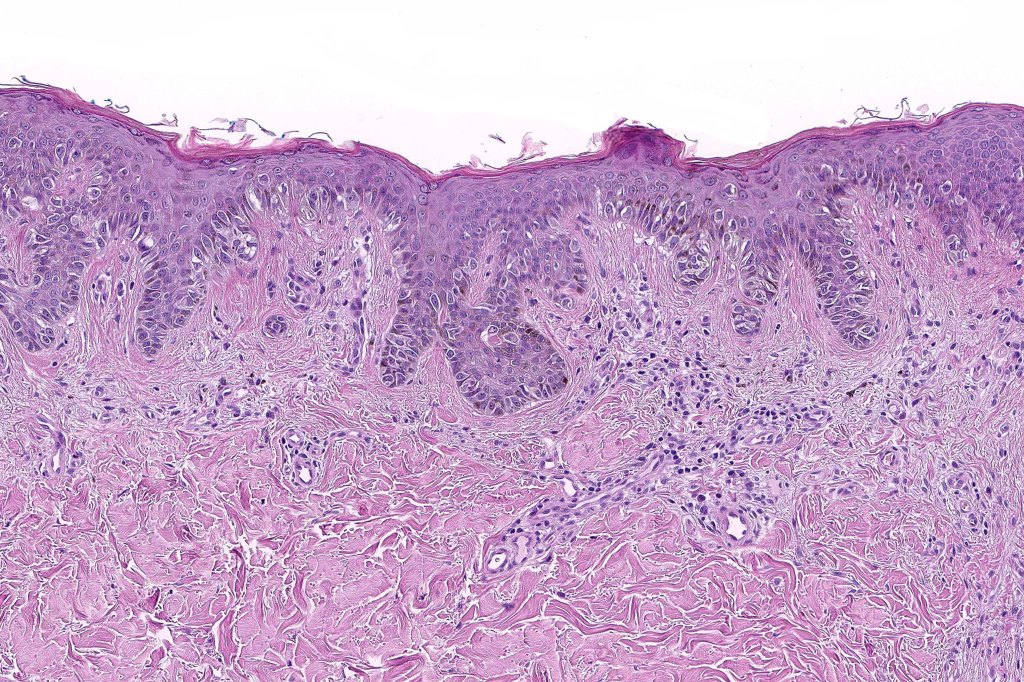

Histological features

•Architectural disorder- lentiginous and nested, nests abnormally located (at the sides of the rete ridges & overlying the dermal papillae in addition to the tips of the rete ridges rather than solely occupying the tips of the rete ridges as is seen in banal nevi), horizontal orientation & bridging between junctional nests (this should not be confused with bridging between adjacent rete ridge squamous epithelium)

•Host response- eosinophilic & lamellar fibroplasia, increased vascularity, lymphocytic infiltration & pigment incontinence

Dysplastic nevus is sometimes confused with early/evolving Reed nevi. The presence of an almost pure population of uniform, spindled melanocytes, often heavily pigmented nested lesion forming a flattened lower border make the distinction fairly straightforward. Reed nevus is symmetrical & circumscribed.